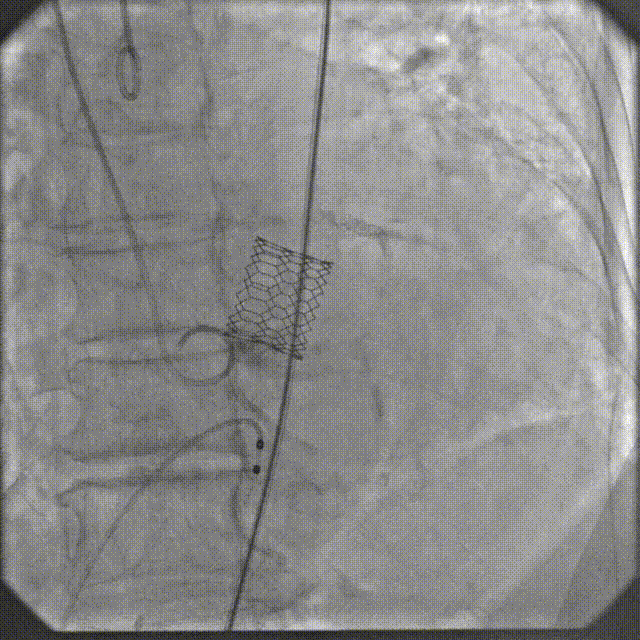

3月30日上午,培训班在重大疾病新药靶发现及新药创制全国重点实验室模式动物工程研究中心开展TAVR手术实操训练,二尖瓣缘对缘修复术器械演示。全体学员在符合GLP标准的实验环境中,使用经病理建模的实验猪进行介入操作演练。该动物模型通过专业培育,其主动脉瓣钙化程度与血流动力学参数可复现人类重度主动脉瓣狭窄的核心病理特征。

在数字减影血管造影(DSA)与经胸超声(TTE)双模影像引导下,学员系统完成经导管主动脉瓣置换术全流程操作:首先建立经皮腹主动脉穿刺入路,随后进行导丝跨瓣定位,继而操控人工瓣膜输送系统,最终实现瓣膜精准释放。训练重点强化三个技术维度:①血管入路建立与并发症预防 ②影像引导下的器械递送路径规划 ③基于实时超声的血流动力学评估。

通过标准化动物实验平台,参训医师不仅掌握了TAVR手术的核心操作规范,更深入理解了影像学参数与解剖结构动态匹配的决策逻辑。该训练体系通过量化评估穿刺成功率、瓣膜定位精度及操作时效性等核心指标,为临床技术转化建立可追溯的质量控制标准。